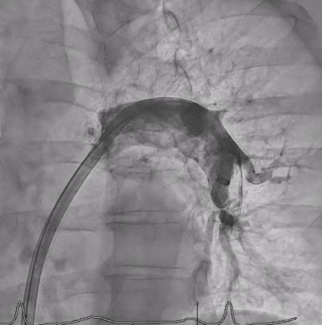

A 69-year-old man was referred for percutaneous coronary intervention of a right coronary artery in-stent complete total occlusion, which had collateral supply from the left anterior descending artery.